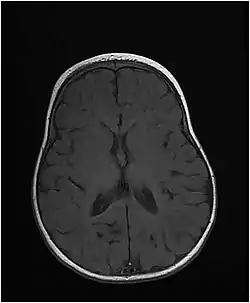

| Axial T1-weighted MRI of the brain at 10 months old showing under-myelination of the internal capsules, relative under-myelination of the remainder of the subcortical white matter, and a thin corpus callosum. From an MTHFS deficiency case report by Romero et al., 2019.[1] | |

The disease starts at birth or in early infancy and presents with microcephaly, short stature, and developmental delay. Patients develop seizures that may be hard to control. Brain imaging shows delayed myelination and hypomyelination.[2] Mutations of the MTHFS gene disrupt folate metabolism, which is very important for the proper development of the nervous system and myelination of nerve fibers.[2]